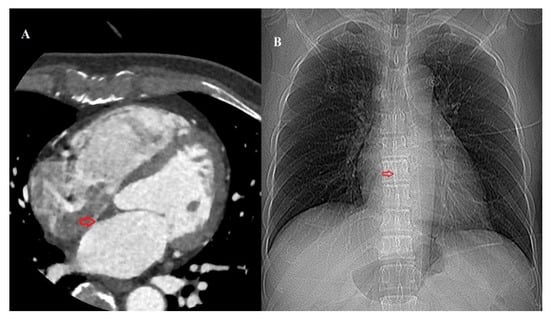

2.3. Image Acquisition and Measurement